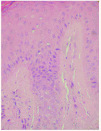

Se realizó una biopsia cutánea observándose una epidermis con hiperqueratosis compacta sin paraqueratosis, y mínimo infiltrado inflamatorio en la dermis. Se detectaban múltiples cuerpos de leishmania en dermis papilar y reticular, tanto en el interior de los macrófagos como libres entre los haces de colágena, y alrededor de las glándulas ecrinas. Se encontraron amastigotes en queratinocitos basales y en número muy escaso en estratos medios de la epidermis; en cambio, existían en gran cantidad en el interior de los acrosiringios, en los ductos ecrinos y en las glándulas ecrinas subyacentes (fig. 4).

Fig. 4.--Eliminación de leishmanias a través de los acrosiringios. (Hematoxilina-eosina, x400.)